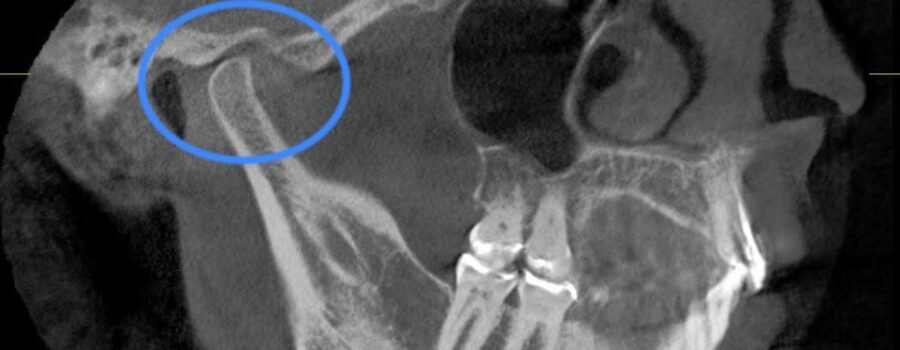

The major component of diagnosis in our office is cone-beam CT (CBCT) analysis, Jaw Tracking, Transcutaneous Electrical Neural Stimulation (TENS), Electromyograph (EMG), and Jaw Joint Sonograph. These instruments have been used for years in medical specialties and are now being used in dentistry to measure postural balance and muscle dysfunction of the jaw, which is the major culprit in the majority of patients reporting headache profiles.